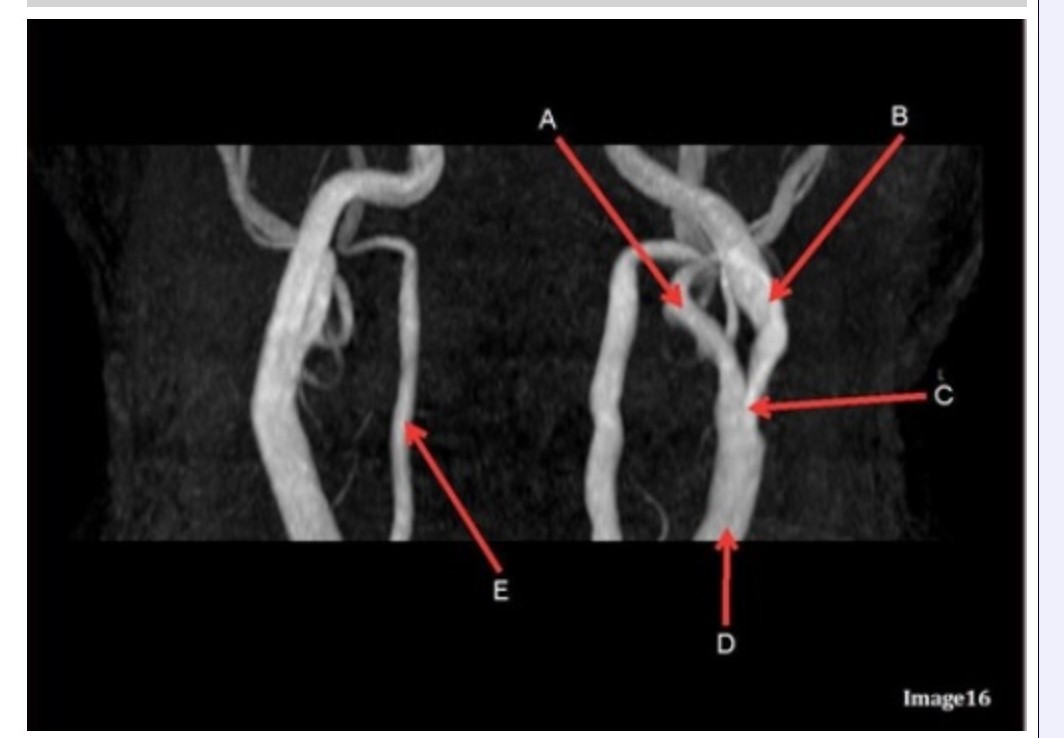

Letter B in Image 16 is pointing to:

A. Internal carotid artery

B. External carotid artery

C. Vertebral artery

D. Common carotid artery

E. Common carotid bifurcation

Letter E in Image 16 is responsible for blood supply to the:

A. Anterior brain

B. Posterior brain

C. Face

D. Upper extremities

Letter D in Image 16 is pointing to:

A. Internal carotid artery

B. External carotid artery

C. Vertebral artery

D. Common carotid artery

E. Common carotid bifurcation

Image 16 is an example of what type of MR image?

A. MR spectroscopy

B. MRA Circle of Willis

C. MRV intracranial circulation

D. MRA extracranial circulation

E. MRA intracranial circulation

Letter B in Image 16 is responsible for blood supply to the:

A. Anterior brain

B. Posterior brain

C. Face

D. Upper extremities

Letter E in Image 16 is pointing to:

A. Internal carotid artery

B. External carotid artery

C. Vertebral artery

D. Common carotid artery

Letter C in Image 16 is pointing to:

A. Internal carotid artery

B. External carotid artery

C. Vertebral artery

D. Common carotid artery

E. Common carotid bifurcation

Letter A in Image 16 is pointing to:

A. Internal carotid artery

B. External carotid artery

C. Vertebral artery

D. Common carotid artery

E. Common carotid bifurcation

Letter A in Image 16 is responsible for blood supply to the:

A. Anterior brain

B. Posterior brain

C. Face

D. Upper extremities